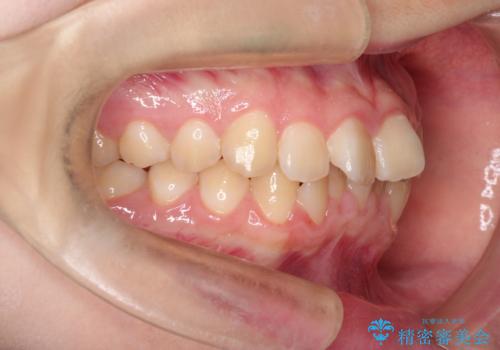

なるべく通院回数を減らして矯正したい インビザラインでのガタガタ矯正

- 10代女性

- インビザライン

- 1年2ヶ月

- 上下の歯並びを治したいとのことで来院されました。

受験生ということもあり、なるべく通院回数を減らしての矯正を希望されたので、インビザラインで治療をすることにしました。